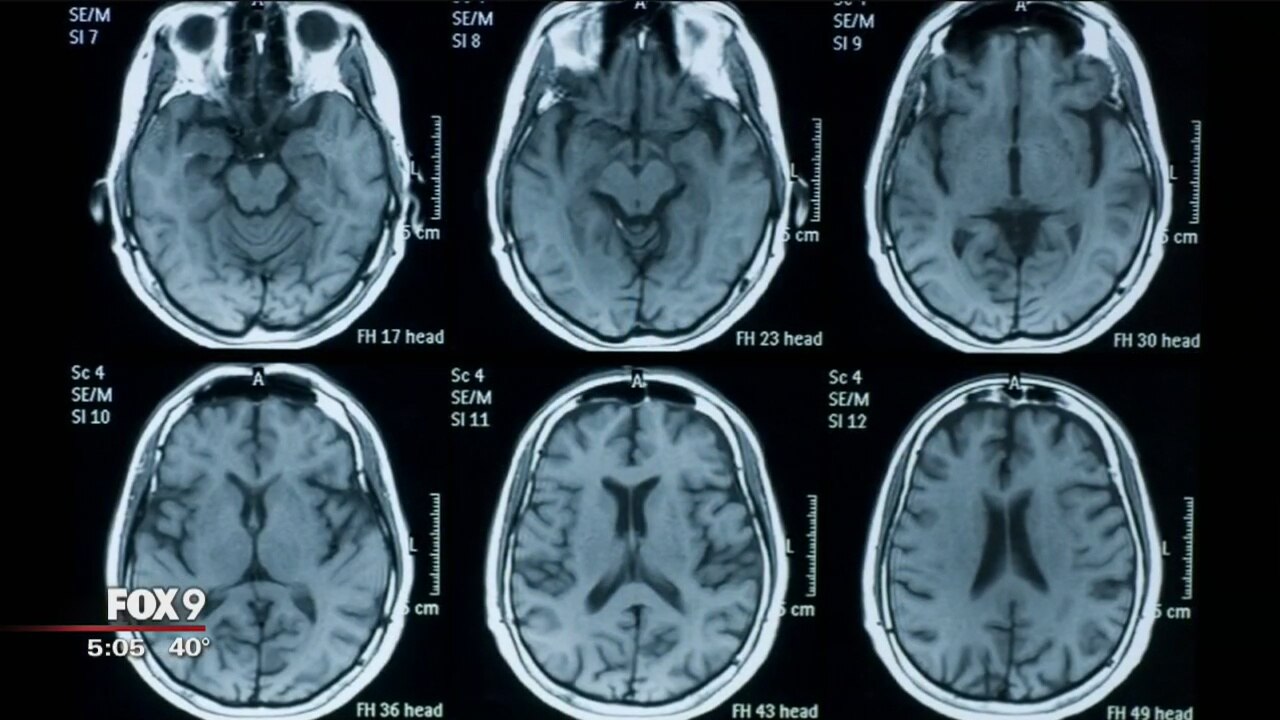

Researchers from three different Twin Cities hospitals are collaborating on a new study that will help them better identify and treat traumatic brain injuries, including concussions.